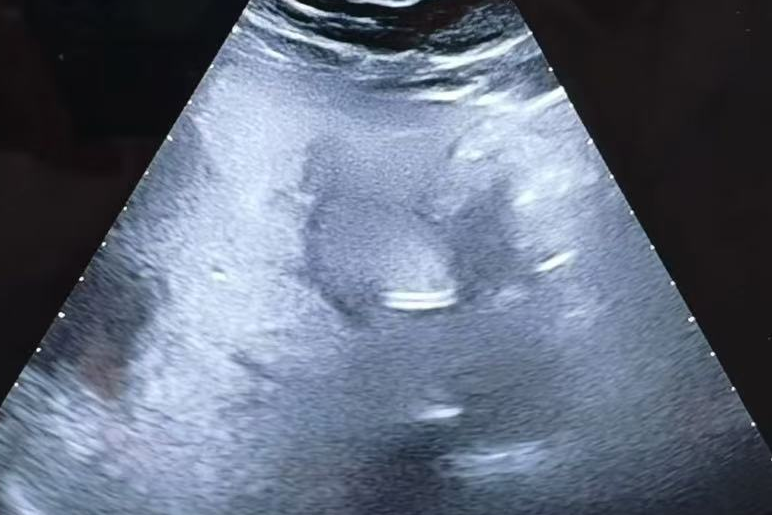

手术前,刘志龙教授通过详细问诊、全面体格检查及辅助检查结果分析,对患者病情做出了充分评估。他还亲自操作肝脏超声,精确评估肝囊肿状况。结果显示,患者肝囊肿直径超过5cm且伴有上腹不适,硬化治疗指征明确。刘教授随后耐心地与患者及家属沟通病情与手术方案,逐一解答疑问,使其紧张情绪得到极大缓解,患者及家属最终欣然同意接受治疗。

术前超声评估